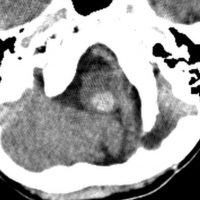

全脳照射後の脳内石灰化(幼児例)

20年以上前のことですが,髄芽腫の1歳6ヶ月の子どもに25グレイの全脳照射をしました。これは15年後のCTです。

脳の萎縮は目立ちません。認知機能は低いのですが支援を受けて学校へ行けています。下垂体機能は低下して成長ホルモンなどの補充をして普通に暮らせています。

CTで,両側の大脳基底核(被殻と淡蒼球)と視床後部に石灰化がみられます。乳幼児期に放射線治療を受けた子どもに見られるものです。